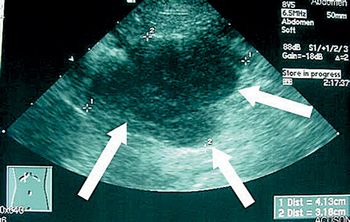

Using ultrasound guidance to perform fine-needle aspiration biopsy is preferred for tumors of the neck.